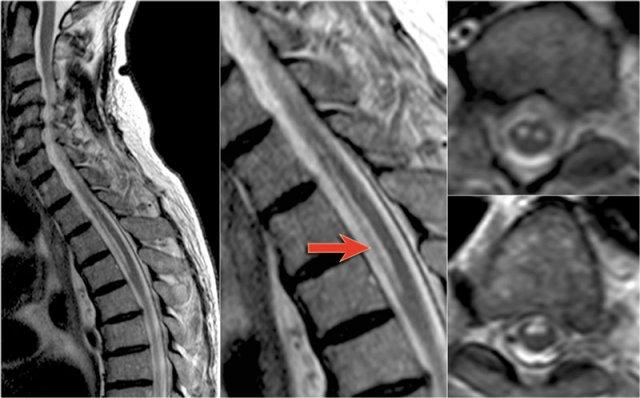

MS là bệnh “bắt chước vĩ đại” và cũng có thể nằm ở phía trước như ở bệnh nhân này, người có tổn thương ở vị trí điển hình (mũi tên xanh) nhưng cũng có tổn thương ở phía bụng của tủy (mũi tên đỏ).

Điều này không phổ biến, nhưng bạn không thể loại trừ MS.

Đây là hình ảnh của bệnh nhân MS lâu năm đang trong đợt cấp.

Có sự ngấm thuốc ở các tổn thương đang hoạt động.

Tiếp tục xem các hình ảnh của cột sống cổ.

Trong tủy sống cũng có nhiều tổn thương.

Trên hình ảnh cắt ngang thấy một tổn thương phía lưng hình tam giác điển hình.

Tiếp tục xem các hình ảnh sau tiêm thuốc tương phản từ.

Ở tủy sống cũng có nhiều tổn thương MS ngấm thuốc.